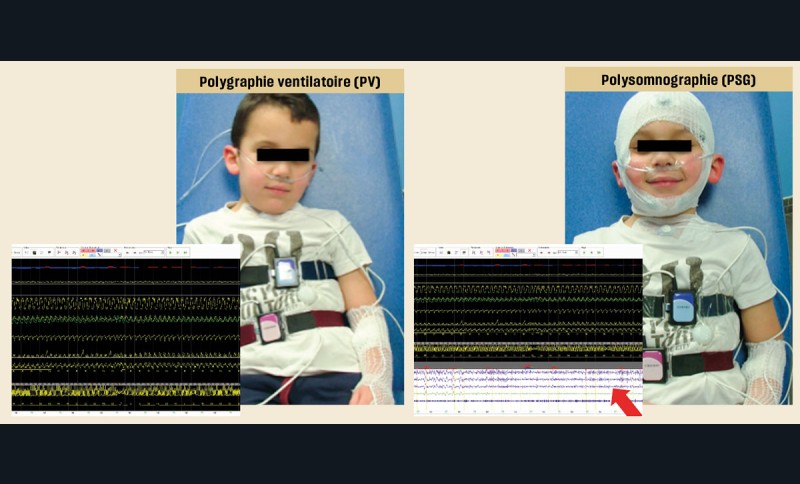

Lorsqu’un enregistrement du sommeil est nécessaire (Sahos clinique sans obstacle ou Sahos clinique avec obstacle ORL chez un enfant à risque), il est réalisé préférentiellement une polysomnographie en milieu hospitalier avec capnographie. En l’absence de facteur de risque, une polysomnographie ambulatoire ou une polygraphie ventilatoire (sans analyse du sommeil) peuvent être proposées si elles sont plus acceptables ou plus accessibles (fig. 4). Tout résultat de polygraphie ventilatoire discordant avec la clinique doit être contrôlé par un enregistrement polysomnographique.

La Fédération française d’orthodontie recommande la surveillance de l’absence de Sahos résiduel à la suite d’une prise en charge orthodontique en adressant le patient traité aux autres professionnels de l’équipe pluridisciplinaire [20]. De même, la société française d’ORL recommande un enregistrement du sommeil par Polysomnographie (PSG) 3 à 6 mois après la fin de traitement, quel que soit le type de prise en charge [39]. Il est nécessaire d’adresser le patient dès que possible en cas de suspicion de Sahos résiduel, l’enregistrement du sommeil par PSG étant le moyen le plus fiable de le détecter [44].

Le Sahos chez l’adolescent est mal individualisé et classé comme une forme de transition entre celui de l’enfant et celui de l’adulte. Les facteurs de risque sont similaires à ceux retrouvés chez l’enfant (obésité, présence d’anomalies cranio-faciales). Le diagnostic est difficile puisque certaines de ses manifestations telles que la fatigue, la somnolence et les troubles dépressifs sont assez communs pendant l’adolescence. Comme pour le Sahos de l’enfant, le diagnostic est établi sur l’ensemble des données recueillies lors de l’examen clinique ainsi que des antécédents médicaux du patient, et il est confirmé par l’enregistrement du sommeil (PSG) [45-47].